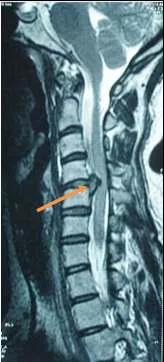

脊髓型颈椎病突出的椎间盘压迫脊髓

脊髓型颈椎病:是颈椎病最严重的一种类型,由于颈椎间盘突出、后纵韧带钙化、黄韧带肥厚压迫脊髓,患者出现颈部僵硬,四肢无力、麻木明显,双足有踩棉感,手脚不灵活,呈紧张步态或醉酒步态等症状,病程长者出现四肢肌肉萎缩,严重者有大小便及性功能障碍。